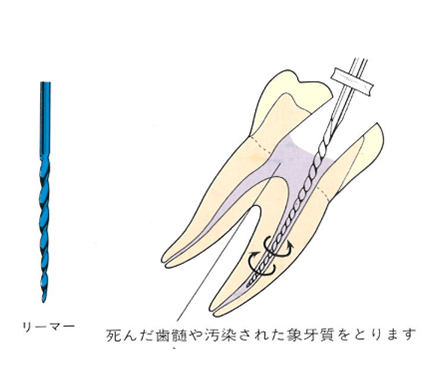

虫歯菌に侵された神経(歯髄)や汚染された象牙質をリーマー、Kファイル、Hファイルなどを使用して取り除いていきます。

ファイルやリーマーを使用して神経を取ります。